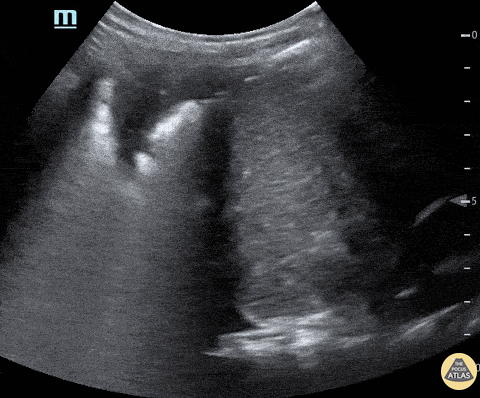

A child with history of sickle cell presented with upper abdominal and back pain and was found to be tachypneic with low grade fever. Ultrasound of the left upper quadrant demonstrated basilar left lung consolidation. Subsequent chest x-ray was interpreted as infiltrate consistent with acute chest syndrome. Michael Cover, @michaelc0ver